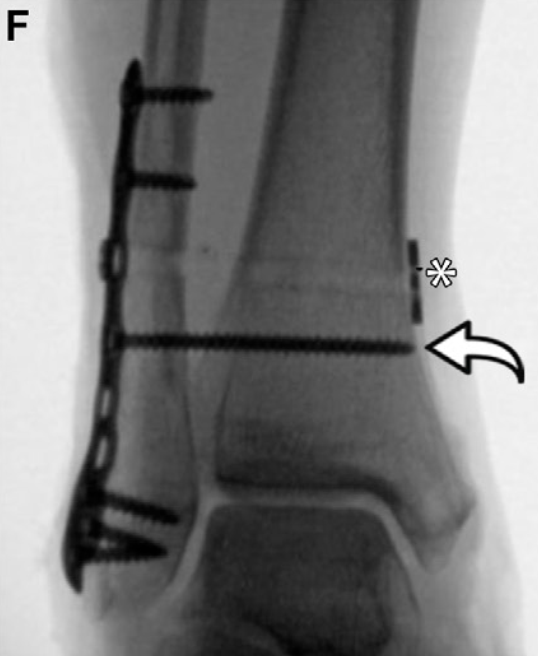

刚性螺钉固定带来的生物力学负荷,会引发多种并发症,包括胫腓联合复位不良、螺钉松动、螺钉移位和螺钉断裂,这些并发症均可能需要取出螺钉:

上述并发症可能无明显的临床症状,从而延误对疼痛性螺钉或持续性胫腓联合不稳的发现和干预。放射科医生需在影像学检查中识别这些异常并予以提示,但同时也应注意,若胫腓联合已实现良好的愈合复位,螺钉周围的松动或螺钉断裂可能无临床症状,甚至提示胫腓联合的生理活动已部分恢复。

缝线纽扣装置可能导致的并发症包括:固定稳定性不足或失效、结刺激、无菌性骨溶解和/或感染。缝线纽扣装置的取出率低于螺钉固定,这一特点也为其成本效益优于螺钉固定的观点提供了支持。

胫腓联合翻修手术最常见的指征为:初次固定后出现复发性分离或复位丢失。